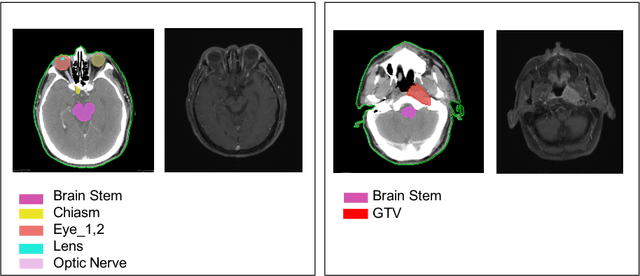

Abstract:With the development of image segmentation in computer vision, biomedical image segmentation have achieved remarkable progress on brain tumor segmentation and Organ At Risk (OAR) segmentation. However, most of the research only uses single modality such as Computed Tomography (CT) scans while in real world scenario doctors often use multiple modalities to get more accurate result. To better leverage different modalities, we have collected a large dataset consists of 136 cases with CT and MR images which diagnosed with nasopharyngeal cancer. In this paper, we propose to use Generative Adversarial Network to perform CT to MR transformation to synthesize MR images instead of aligning two modalities. The synthesized MR can be jointly trained with CT to achieve better performance. In addition, we use instance segmentation model to extend the OAR segmentation task to segment both organs and tumor region. The collected dataset will be made public soon.